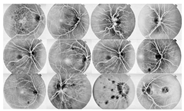

where f(vessel, background) corresponds to the input image, g(vessel, background) denotes the binary pixel after thresholding, and 128 is the optimal value to classify the histograms between the two classes. Any pixel (vessel, background) in the image at which f(vessel, background) ≥ 128 is extracted as a vessel pixel; otherwise, the pixel is regarded as a background point or a non-vessel pixel. The extraction result is displayed in Figure 8, where pixels with intensity values greater than 128 (retinal blood-vessel pixels) are shown in white against a background of black. As shown on the left side of Figure 8a, there are a few false extractions; they segment the actual retinal blood vessels (white pixel) as the background (black pixel). The Dilatation-Based Function is added to optimal thresholding functions to reduce the false negative value (see Figure 8b).

Figure 8.

Comparison of the extraction results with WKFCM false extraction and adding morphological dilation operator: (a) intensity thresholding with a loose extraction using WKFCM, (b) intensity thresholding using the proposed Dilatation-Based Function technique (demonstrated within the blue line).

where the extracted image’s pixel value is |SM| and the ground-truth image’s pixel value is |GT|, while |GT∩SM| represents the common elements between the ground-truth and the extracted images, and |GT + SM| represents the total number of pixels in the image. The addition of the proposed improvement of the WKFCM method to the extraction, based on the morphological dilation functions and optimal global thresholding, is displayed at the right of Figure 9. I confirmed that false extraction values were reduced and proposed a more accurate image of vessel extraction.

Figure 9.

Cross-dataset extraction result comparison of the retinal images from three datasets: (a) DRIVE dataset (first row), (b) STARE dataset (second row), (c) DiaretDB0 dataset (third row).

4.3. Analysis of Proposed Blood-Vessel Extraction

The proposed method was simulated within a MATLAB environment (The Mathworks, Inc.) and executed on a personal computer with an Intel (R) Core (TM) i7-6700K CPU at 4.00 GHz and 8 GB DDR3 RAM. To confirm the proposed method in retinal vessel extraction, I visualized and compared the activations from the different stages presented. Figure 9 shows a visual comparison of three extracted images from the DRIVE, STARE, and DiaretDB0 datasets by the proposed method. The parameters provided in Equations (19)–(21) were used for the proposed method. Their average was determined by applying the traditional FCM and the proposed WKFACM-DBF method with a non-enhanced and an enhanced image to 167 test images of the DRIVE, STARE, and DiaretDB0 datasets, as shown in Table 2 and Table 3, respectively.